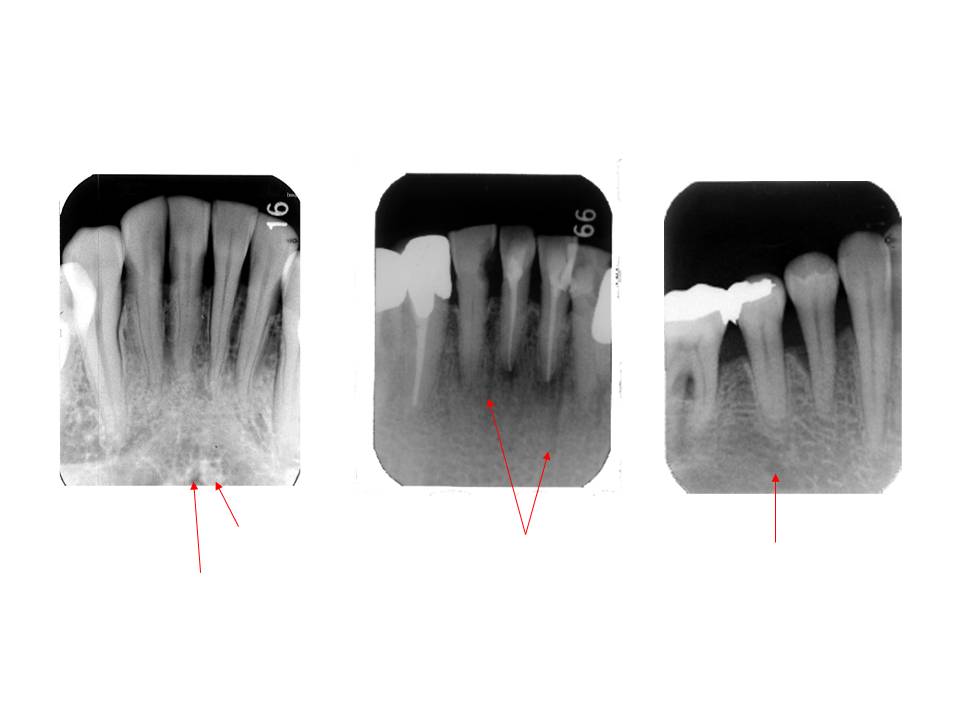

口内法(二等分法・咬合法)撮影の解剖